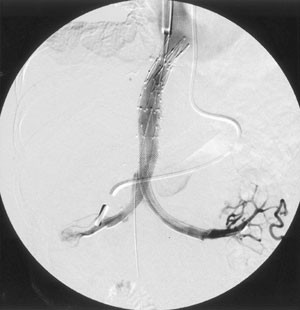

Percutaneous Stent Placement as Treatment of Renal Vein Obstruction Due to Inferior Vena Caval Thrombosis

A patient who had undergone his third orthotopic liver transplantation nearly 9 years prior to presentation developed worsening hepatic and renal function, as well as severe bilateral lower extremity edema. Magnetic resonance imaging demonstrated vena caval thrombosis from the suprahepatic venous anastomosis to the infrarenal inferior vena cava, obstructing the renal veins. This was treated by percutaneous placement of metallic stents from the renal veins to the right atrium. At 16 months clinical follow-up, the patient continues to do well.

Figure 4